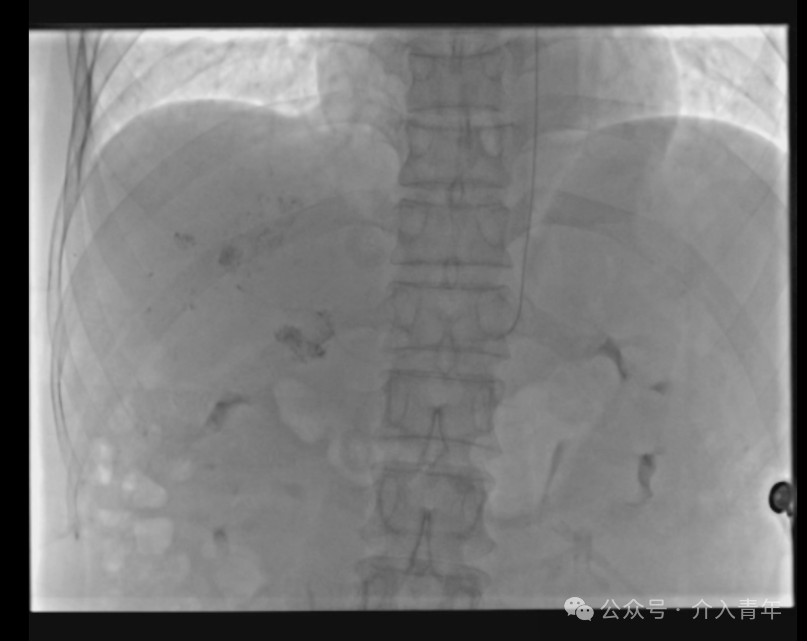

首先将造影导管送入肝固有动脉中,推荐使用4F或5F的MPA1导管,一般都能够顺利超选入肝固有动脉,这一步是后续操作的基础。

用3m的微导丝超选入肝动脉远端固定,笔者使用的是波科V-18导丝,超硬。

微导丝超选入肝动脉远端固定,交换出造影导管,通过长导丝置入微导管,退出导丝术式即成(交换操作均由笔者单人完成,当然双人会更好完成)。